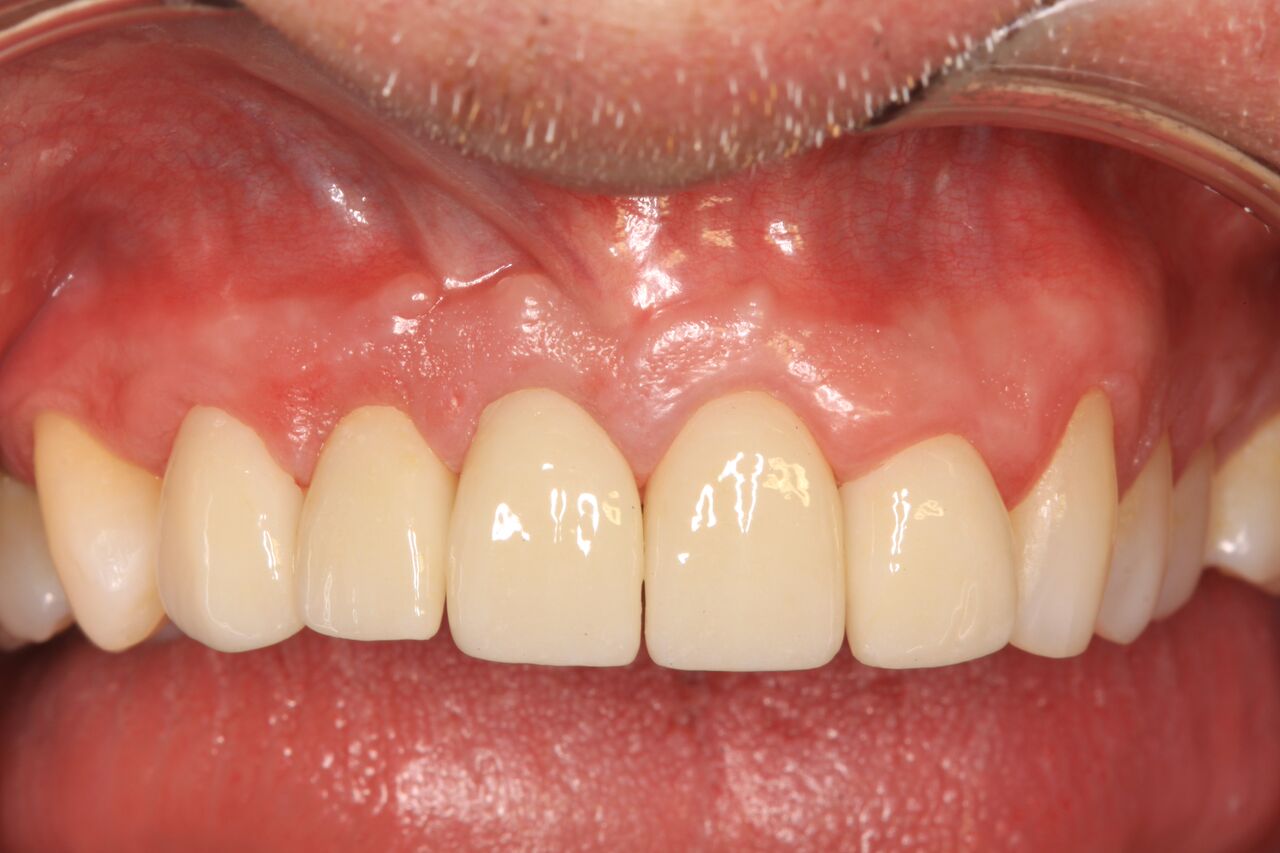

A 42-year-old man presented with a very loose bridge on Nos. 6 through 9 with periodontally compromised retainers on Nos. 6 and 9 (Figure 17 through Figure 19), and endodontically involved No. 10 with a calcified canal. Teeth Nos. 6, 9, and 10 were extracted, the sockets fully debrided, and pontic soft tissue on Nos. 7 and 8 sculpted to be symmetrical in soft tissue contour with the contralateral lateral incisor and central incisor locations. Implants were secured in position Nos. 6 through 10 (Figure 20) in excess of 45 Ncm, the bone was milled to provide unimpeded seating of temporary abutments, and temporary crowns were fabricated chairside and adjusted to be out of occlusion in centric relation and all excursions. The temporary crowns were cemented after extrusion of excess cement extraorally and the patient was prescribed antibiotics, analgesics, and instructed in postoperative care particular to immediately provisionally restored implants. At 6 months, integration was confirmed (Figure 20 through Figure 23) and after placement of scanning abutments, the implants and soft tissues were scanned. Final crowns were fabricated from the scanned images and were cemented after extrusion of excess cement extraorally (Figure 24 through Figure 26), and oral hygiene procedures were reviewed.

(26.) Postoperative individual implant restorations on Nos. 6 through 10.

Figure 26